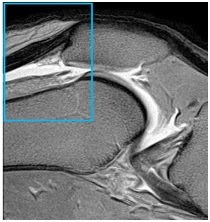

Knee Quadriceps Tendon MRI Graphic